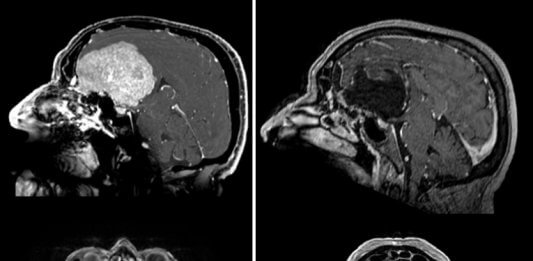

Сибиряк жил с беспричинно хорошим настроением из-за гигантской опухоли в мозге

Новосибирские нейрохирурги спасли 68-летнего пенсионера из Кузбасса, за лечение которого многие не брались из-за слишком сложной ситуации. К признакам наличия у него опухоли головного мозга врачи отнесли не только физиологические отклонения, но и недостаток самокритики и хорошее настроение. Как рассказали в новосибирском НМИЦ имени Мешалкина, изначально поводом для обращения пациента из Кемеровской области к врачам … Читать далее Сибиряк жил с беспричинно хорошим настроением из-за гигантской опухоли в мозге